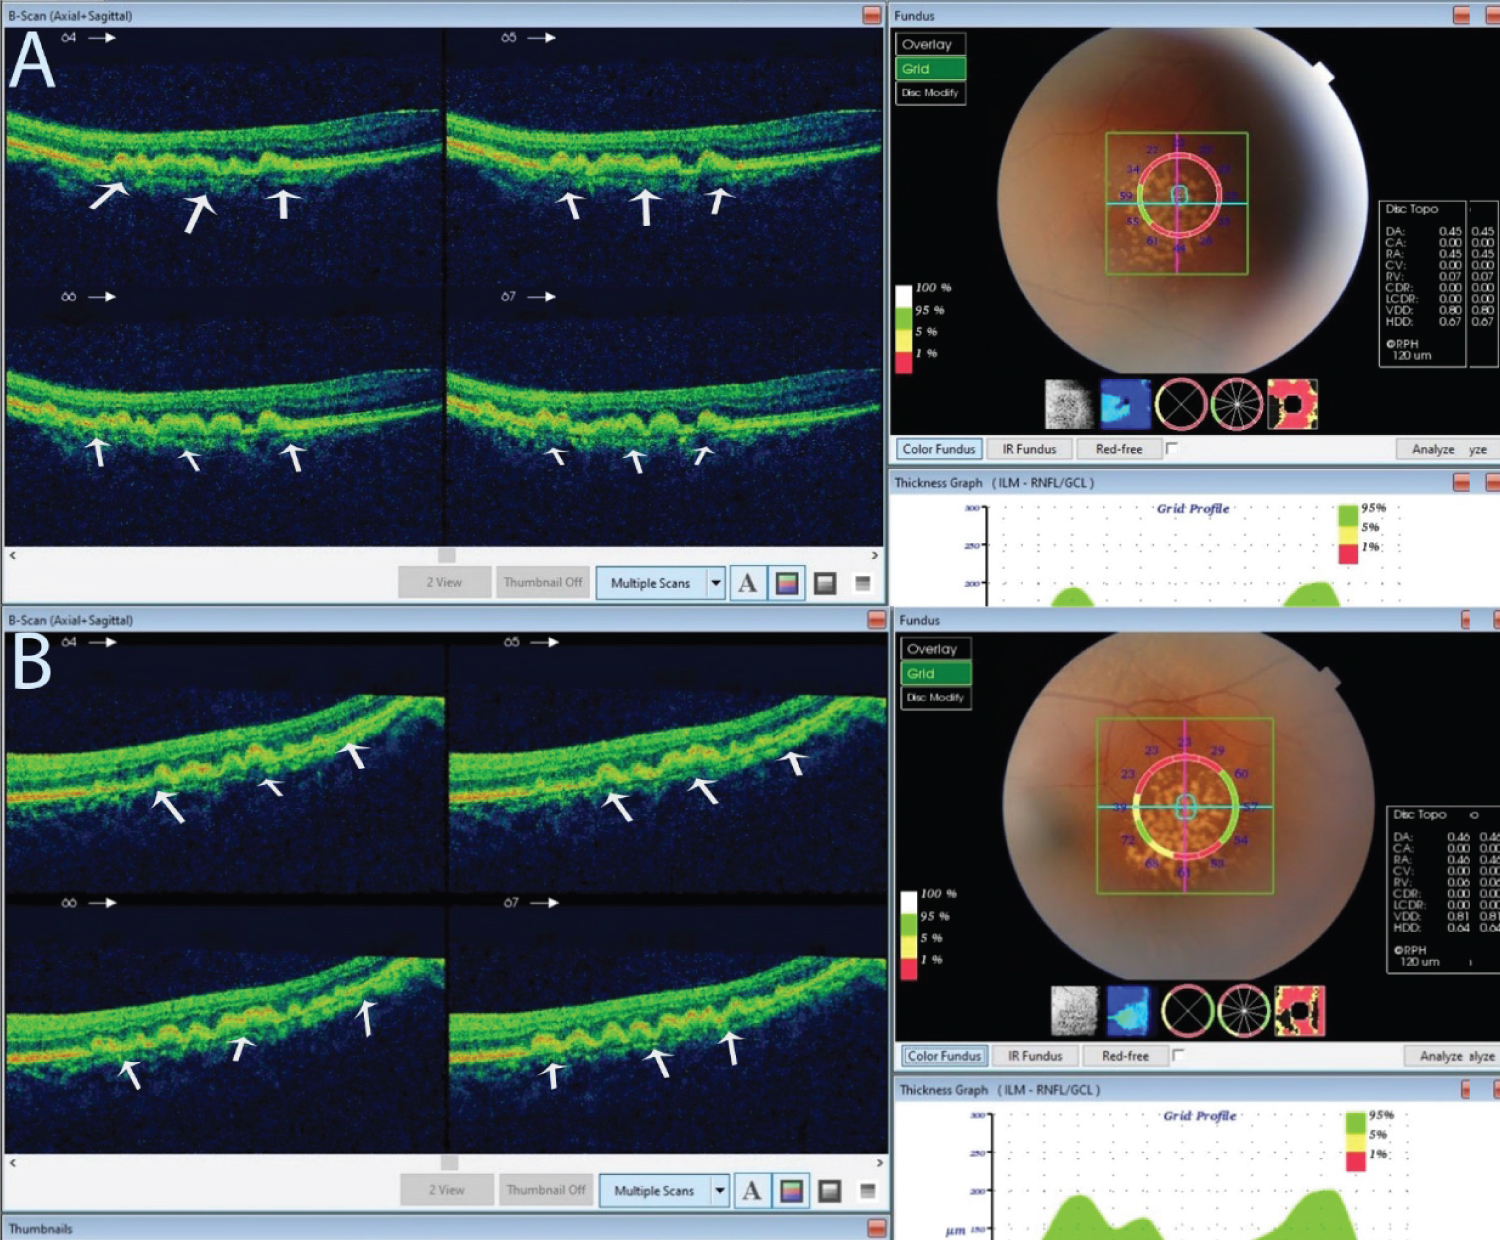

Figure 2: An optical coherence tomography of the lesion described in Figure 1. View Figure 2

Pane A is the right eye and B the left eye. Both show bumps between the retinal pigment epithelium and the Bruch's membrane. These bumps are drusen, indicated by the white arrows.